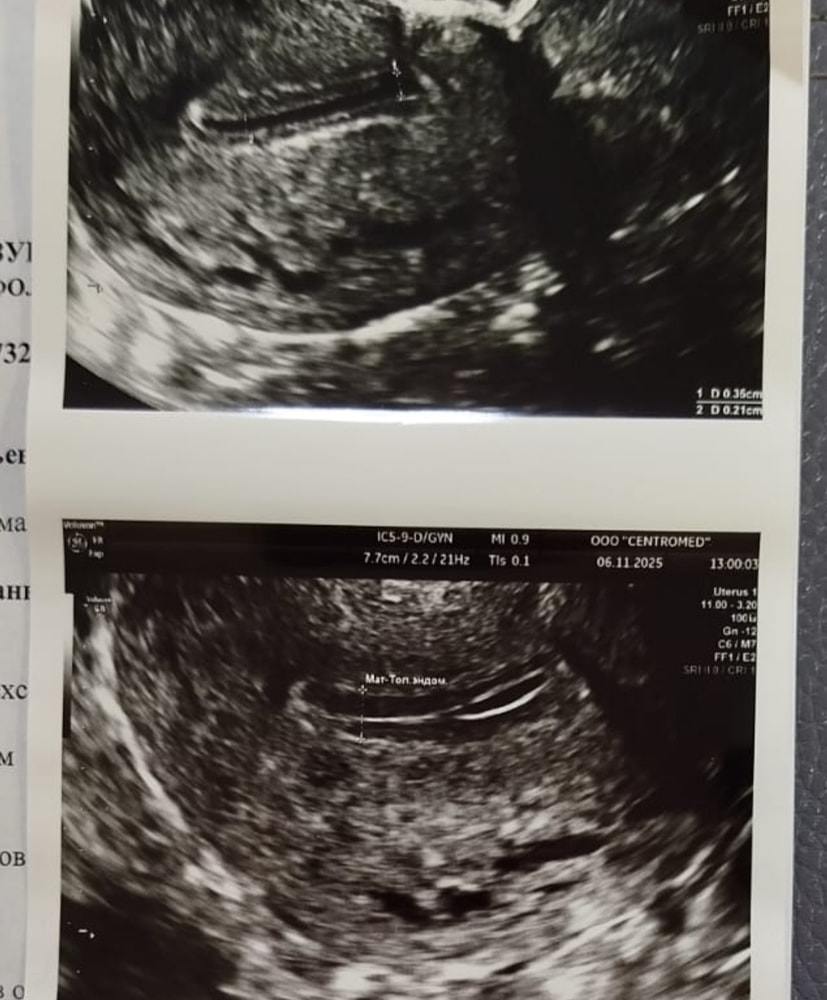

Вот мой эндик хороший до эсрогенов и с жидкостью с приемом прогинова